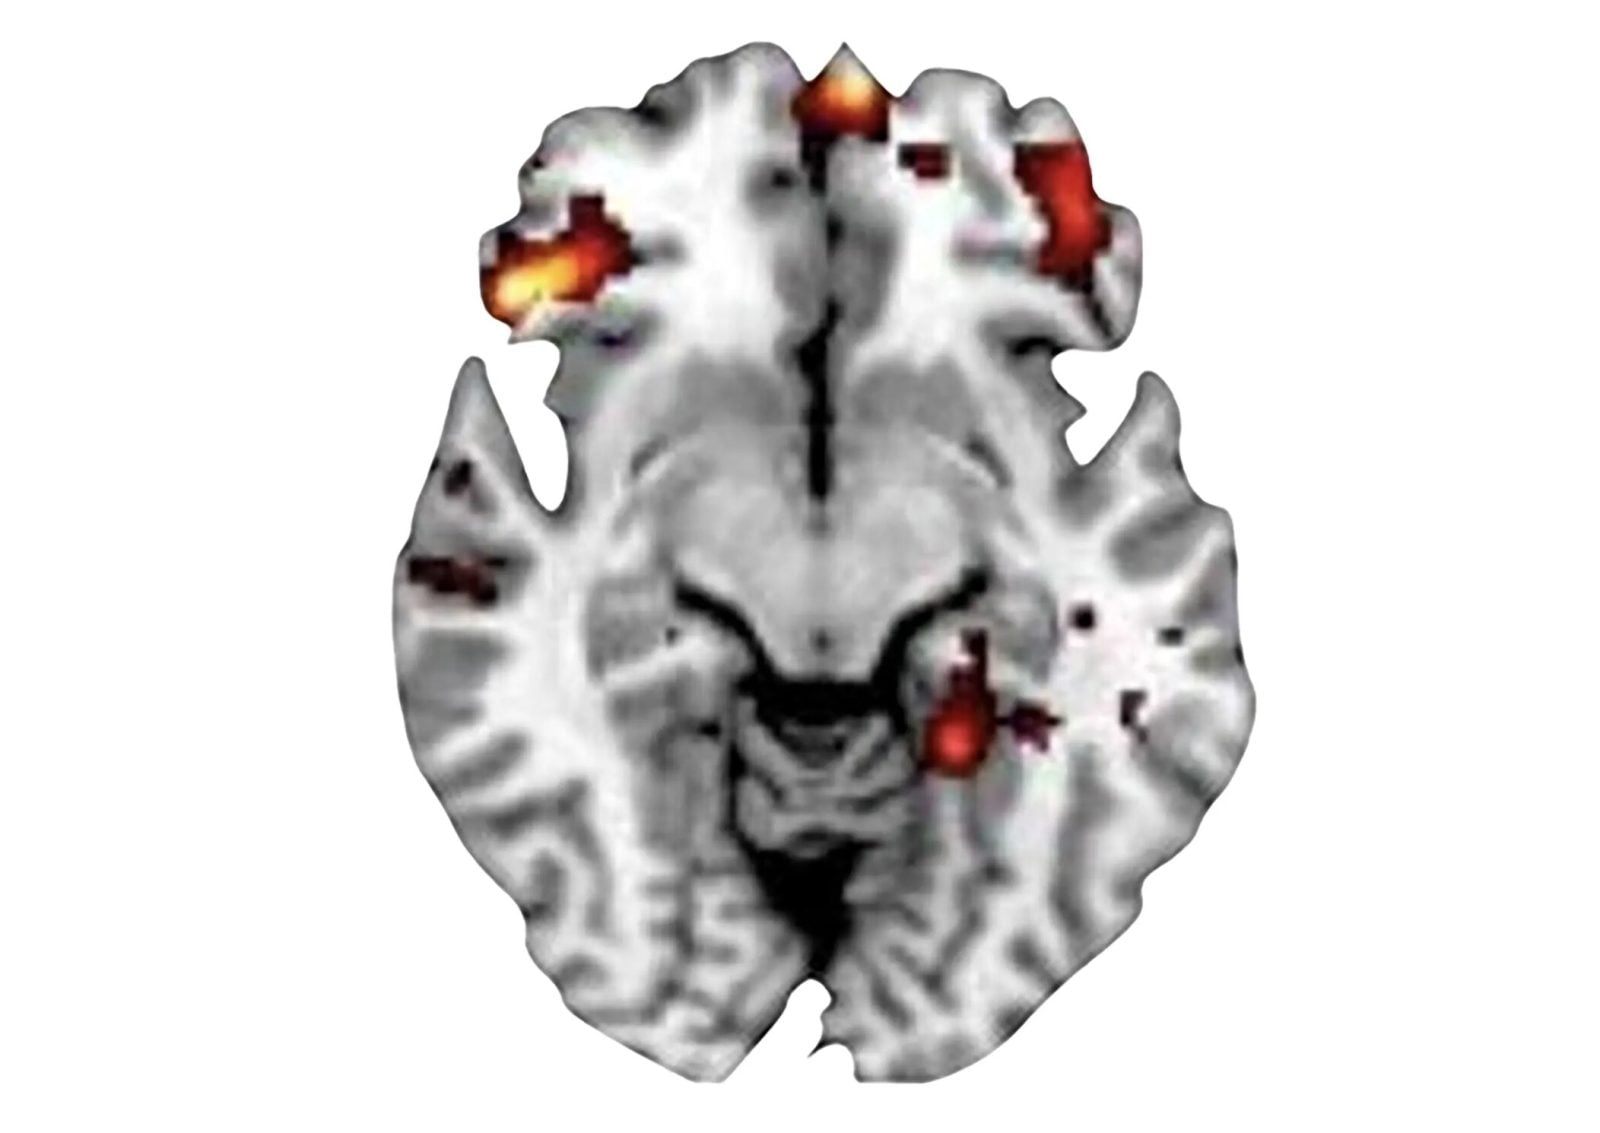

Skany MRI wykazały różne wzorce aktywności mózgu u nastolatków z OCD w porównaniu z grupą kontrolną. Różnice były szczególnie duże w korze oczodołowo-czołowej (OFC), regionie w płacie czołowym zaangażowanym w podejmowanie decyzji i kontrolę zachowania. Podczas zadań związanych z podejmowaniem decyzji boczny OFC wykazywał hipoaktywność u uczestników z OCD, podczas gdy przyśrodkowy OFC wykazywał nadpobudliwość. Naukowcy odkryli również, że nadpobudliwość była powiązana z nasileniem objawów OCD, co potwierdza związek między zdolnością do podejmowania decyzji a zaburzeniem.